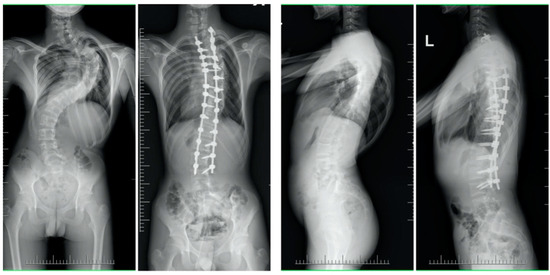

| Mean (SD) preoperative Cobb, deg | 131 (13.8) | 60 (9.5) | <0.001 |

| Mean (SD) Cobb at final follow-up, deg p-value * (pre vs. follow-up) | 61 (19.2) | 18 (9.2) | <0.001 |

| Mean (SD) preoperative thoracic kyphosis T5-T12, deg | 83 (35.9) | 25 (14.2) | <0.001 |

| Mean (SD) thoracic kyphosis T5-T12 at final follow-up, deg p-value * (pre vs. follow-up) | 35 (9.6) | 22 (8.2) | 0.24 |